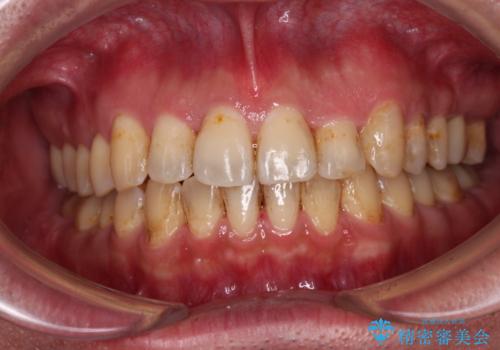

インビザライン矯正では苦手とする舌側転位した前歯をスムーズに改善することができました。

矯正治療により歯磨きがしやすくなったので、虫歯予防のセルフケアが行いやすい環境となりました。